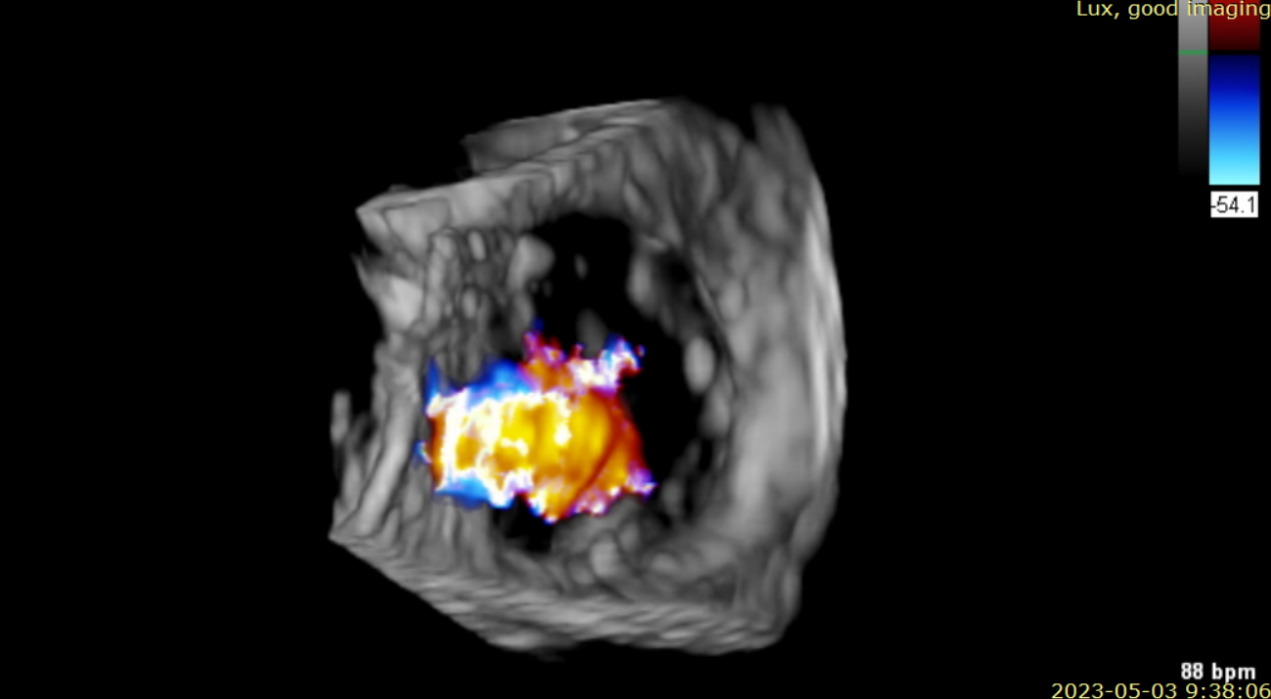

術(shù)前超聲提示大量三尖瓣反流

術(shù)后超聲提示僅殘余輕微瓣周漏